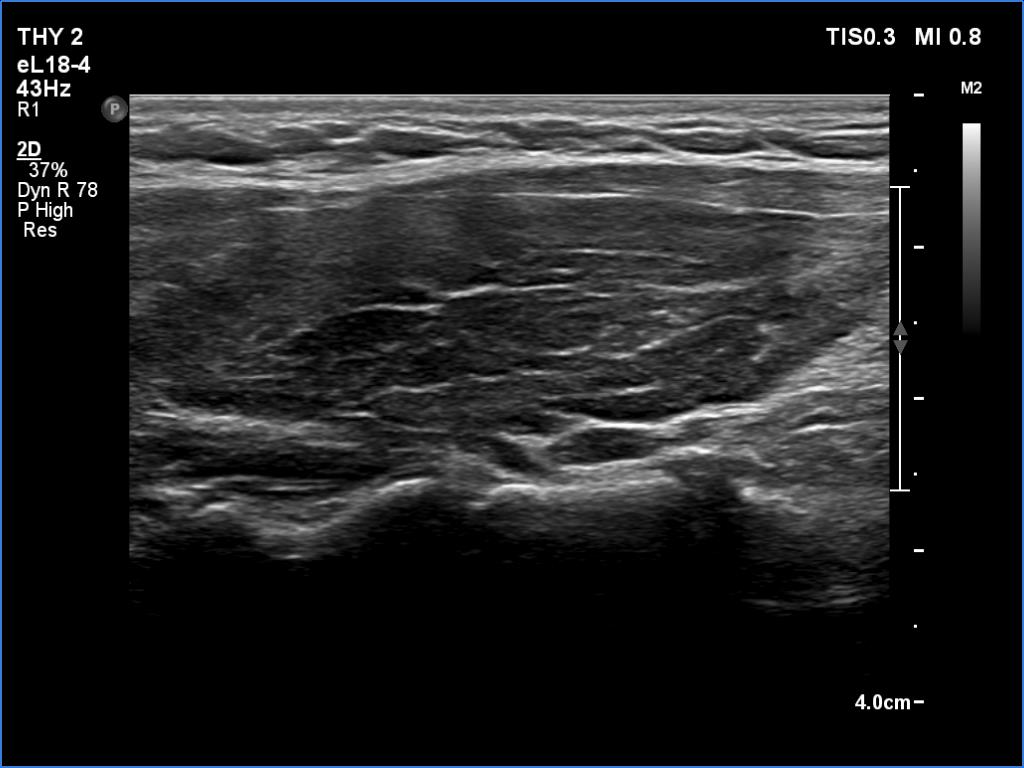

Second examination a year later (second row of images):

Comment. The patient presented a post partum thyroiditis, i.e., the underlying autoimmune thyroiditis became more active. The change in ultrasound pattern is also in line with this. Be aware the rapid change in ultrasound pattern. In other cases, the echogenicity can change in years, rather decades in the case of a hypothyroidism. The structure is expected to show the pattern seen in the first study a year later.Clinical data: Half a year ago, the patient gave birth. She took 100 microgram of medicine a day in the second half of the pregnancy, and after giving birth she returned to the previously used dose of 50 micrograms a day. She gained 8 kg in the last three months and had other symptoms which suggested underdosing.

Palpation: unchanged.

Laboratory tests: TSH 9.88 mIU/L, FT4 7.61 pM/L on daily 50 microgram levothyroxine.

Ultrasonography. In contrast to the previous examination, the entire thyroid became hypoechoic. There were only small islets with less hypoechoic pattern.

Suggestion: to increase the dose of levothyroxine to daily 75 micrograms. Repeat TSH in 6 months.